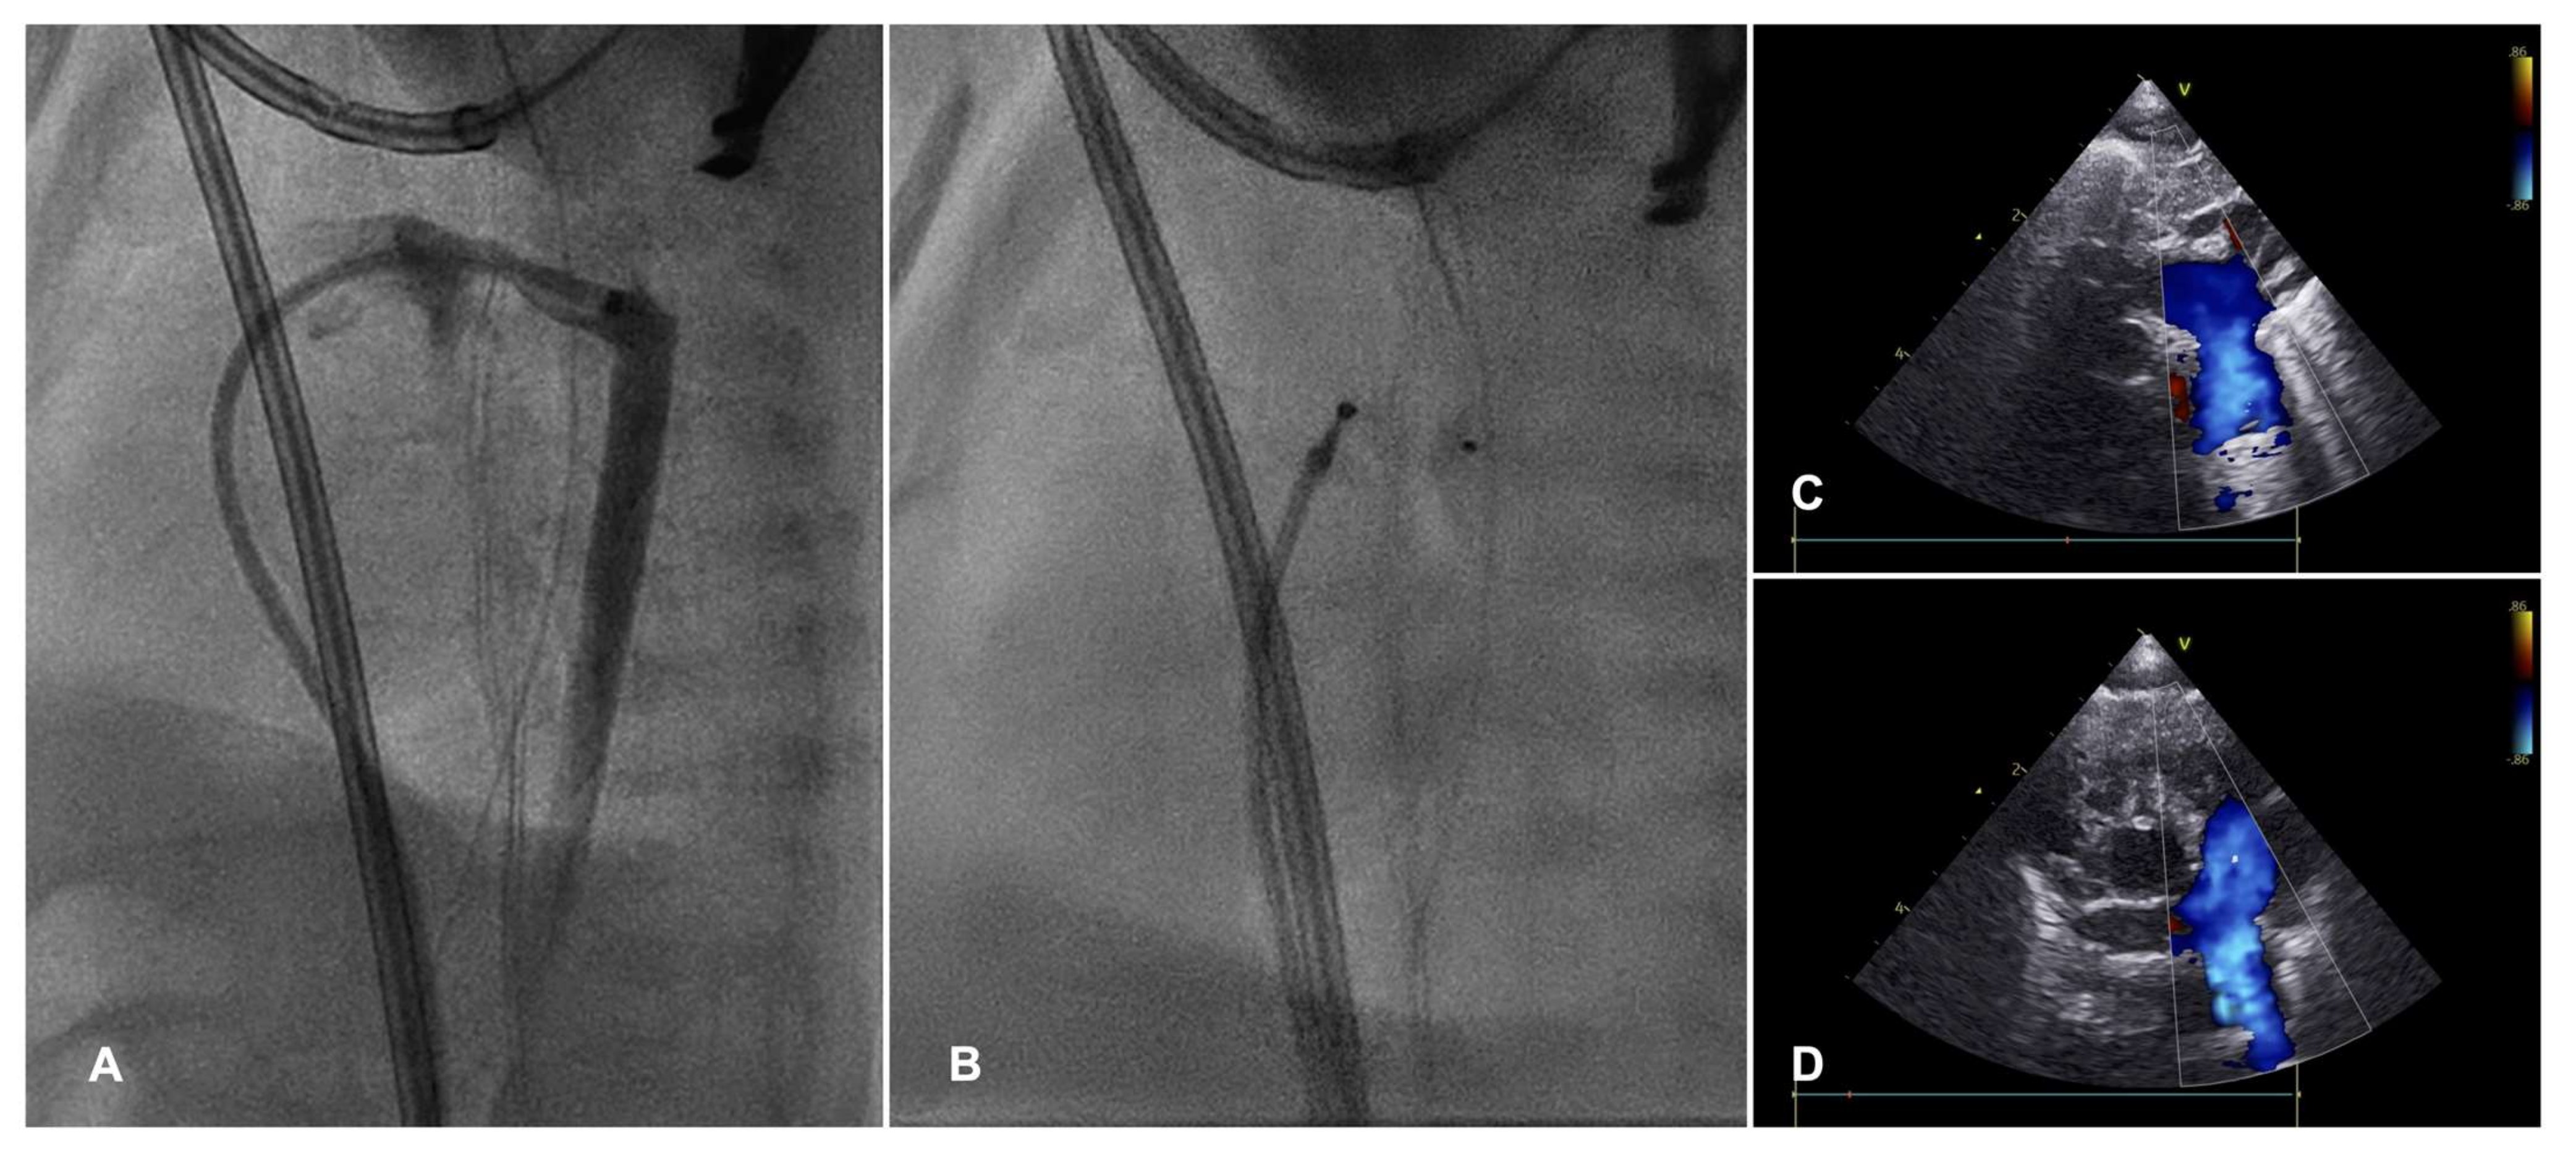

- Zahn, E.M.; Peck, D.; Phillips, A.; Nevin, P.; Basaker, K.; Simmons, C.; McRae, M.E.; Early, T.; Garg, R. Transcatheter Closure of Patent Ductus Arteriosus in Extremely Premature Newborns: Early Results and Midterm Follow-Up. JACC Cardiovasc. Interv. 2016, 9, 2429–2437. [Google Scholar] [CrossRef]

- Sathanandam, S.; Justino, H.; Waller, B.R., 3rd; Radtke, W.; Qureshi, A.M. Initial clinical experience with the Medtronic Micro Vascular Plug™ in transcatheter occlusion of PDAs in extremely premature infants. Catheter. Cardiovasc. Interv. 2017, 89, 1051–1058. [Google Scholar] [CrossRef] [PubMed]

- Sathanandam, S.K.; Gutfinger, D.; O’Brien, L.; Forbes, T.J.; Gillespie, M.J.; Berman, D.P.; Armstrong, A.K.; Shahanavaz, S.; Jones, T.K.; Morray, B.H.; et al. Amplatzer Piccolo Occluder clinical trial for percutaneous closure of the patent ductus arteriosus in patients ≥700 grams. Catheter. Cardiovasc. Interv. 2020, 96, 1266–1276. [Google Scholar] [CrossRef] [PubMed]

- Sathanandam, S.; Balduf, K.; Chilakala, S.; Washington, K.; Allen, K.; Knott-Craig, C.; Rush Waller, B.; Philip, R. Role of Transcatheter patent ductus arteriosus closure in extremely low birth weight infants. Catheter. Cardiovasc. Interv. 2019, 93, 89–96. [Google Scholar] [CrossRef] [PubMed]

- Serrano, R.M.; Madison, M.; Lorant, D.; Hoyer, M.; Alexy, R. Comparison of ‘post-patent ductus arteriosus ligation syndrome’ in premature infants after surgical ligation vs. percutaneous closure. J. Perinatol. 2020, 40, 324–329. [Google Scholar] [CrossRef] [PubMed]